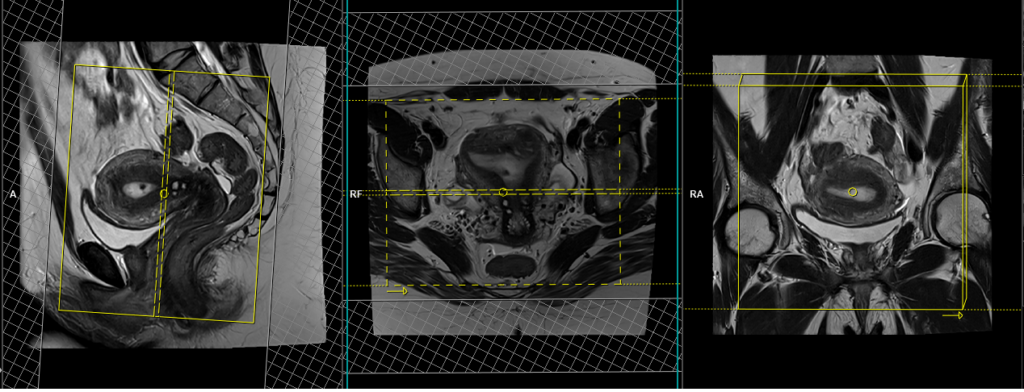

T2 tse axial oblique 3mm SFOV of uterus

Plan the axial oblique slices on the sagittal plane, ensuring that the position block is angled perpendicular to the endometrium. Verify the positioning block in the other two planes. Provide an appropriate angle in theaxial plane (straight across the uterus). The slices must be sufficient to cover the entire uterus and ovaries. Adding saturation bands on top and in front of the axial block will help reduce artifacts caused by arterial pulsation and breathing. Ensure an adequate level of phase oversampling to prevent any wrap-around artifacts.

Parameters

TR 4000-6000 | TE 100-120 | SLICE 3 MM | FLIP 130-150 | PHASE H>F | MATRIX 320X256 | FOV 180-230 | GAP 10% | NEX(AVRAGE) 5 |

T2 tse coronal oblique 3mm SFOV of uterus

Plan the coronal oblique slices on the sagittal plane, ensuring that the position block is angled parallel to the endometrium. Check the positioning block in the other two planes. Ensure an appropriate angle is set in the axial plane (across the uterus). The slices must be sufficient to cover the entire uterus and ovaries. Adding saturation bands on the top and front of the coronal block will help reduce artifacts caused by arterial pulsation and breathing. Ensure an adequate level of phase oversampling to prevent any wrap-around artifacts.

Due to the increased signal-to-noise ratio (SNR) in new generation scanners, motion artifacts can be significant when acquiring images in the anterior-posterior phase direction. This is primarily attributed to the movement of abdominal fat, which exhibits higher signal intensity and can cause ghosting effects over the sagittal images. Therefore, to mitigate this issue, scans are typically performed using a right-to-left phase direction.

TR 3000-4000 | TE 100-120 | SLICE 3 MM | FLIP 130-150 | PHASE R>L | MATRIX 320X256 | FOV 180-230 | GAP 10% | NEX(AVRAGE) 5 |